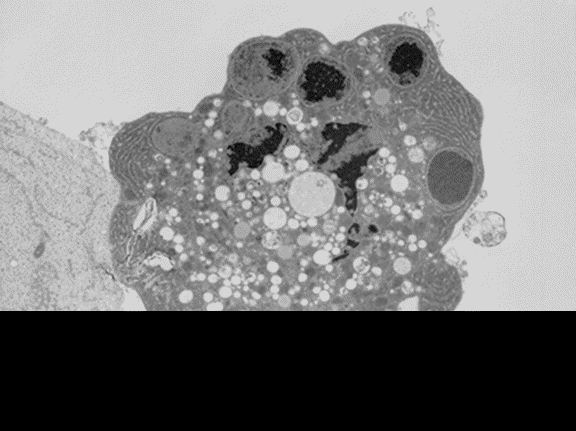

Cuando una célula muere por falta de nutrientes, oxígeno etc (no por un proceso traumático, tóxico o infectivo) entra en un proceso apoptótico que la lleva a la autodestrucción. En ese momento una señal desconocida avisa a una célula madre para que se divida en dos nuevas células, una de las cuales ocupará el lugar de la célula perdida. Gracias al control de la expresión génica, se da esta coordinación en la proliferación celular, para que una pérdida sea compensada con una sola división celular y pueda así preservarse el equilibrio del organismo como conjunto celular. Se define apoptosis como el proceso de muerte celular programada, que ocurre según un patrón predecible y sin causar problemas en el entorno celular, ya que las células que mueren no liberan al medio su contenido, evitando así la necrosis celular, frecuentemente acompañada de proceso inflamatorios. Durante este proceso, el núcleo celular se condensa y la célula es incorporada y degradada rápidamente por sus células vecinas o por macrófagos; una vez dentro del macrófago, la célula apoptótica se fragmenta y sus componentes básicos son reutilizados. El mecanismo apoptótico se desconoce, aunque se sabe que está codificado en el propio genoma celular y se ha conservado a lo largo de la evolución. Una célula que entra en apoptosis cambia su composición química externa para ser reconocida por el macrófago. El procedimiento varía según el tipo de tejido; proteínas como leptinas e integrinas parecen intervenir en tal proceso de reconocimiento. Una segunda razón para que el proceso inflamatorio no acompañe a la apoptosis es que en este caso los macrófagos no generan señales inductoras de la inflamación, como ocurre por ejemplo al fagocitar un microorganismo. El proceso de apoptosis es, pues, la segunda vía de control del número celular, para preservar el preciado equilibrio de un organismo complejo.

La imagen muestra una célula que ha entrado en proceso de apoptosis.